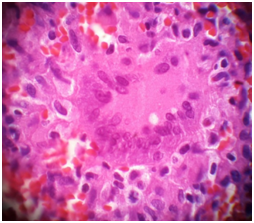

Figure 4 Show Giant cell in the granulomas.

A 72-year-old man presented with history of left thyroid lobe swelling for 5-7month, which was gradually increasing in size with no compressive of neck structure or any associated symptoms. On physical examination, he had a left thyroid cystic and solid nodule.The nodule was no tender and moving with swallowing. Lymph node was not palpable in the neck. The systemic examination was normal, clinically he was euthyroid. Ultrasound of thyroid showed a left sided show cystic and solid nodule. CT-scan of neck with IV contrast shows a solid and cystic mass with peripheral vascularity. The right lobe was normal in size with few small solid and cystic nodules (Figure 5). Her chest X-ray was normal. His CRP, ESR and complete blood count and routine biochemistry were normal.FNA of left thyroid lobe in two time was performed which showed pus material. Cytology revealed follicular lesion. AFB in aspirated pus by Ziehl Nelsen stain was negative. Culture for bacterial and tuberculosis was negative too. He underwent left lobectomy and istmectomy, and her histopathology report showed granulomatous inflammation in the left lobe. With pathologic finding of chronic granulomatous inflammation along with necrosis and with possibility of tuberculosis in the left lobe (Figure 6), he was started on antituberclusis treatment with four drug regimen for the first 2months followed by three drugs regimen for the next 4months along with. He completed her treatment and in follow-up remained asymptomatic.T4, T3 and TSH was in normal range.

Figure 5 CT-scan of neck show a cystic lesion in thyroid.

Figure 6 A necrotizing granuloma H& E X 400.